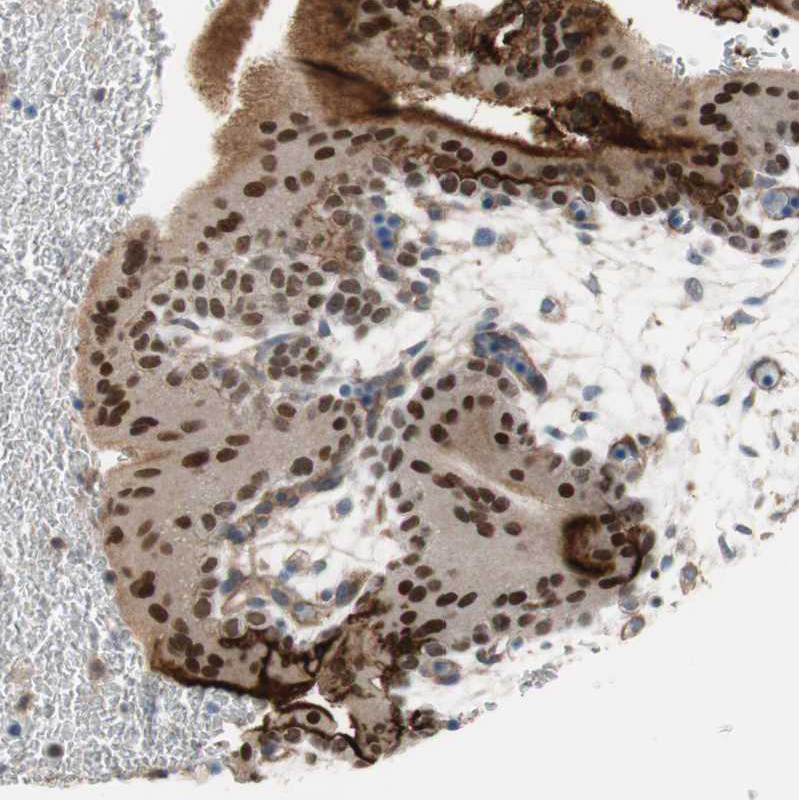

Immunohistochemistry analysis in human skin and skeletal muscle tissues using HPA005798 antibody. Corresponding GRHL1 RNA-seq data are presented for the same tissues.